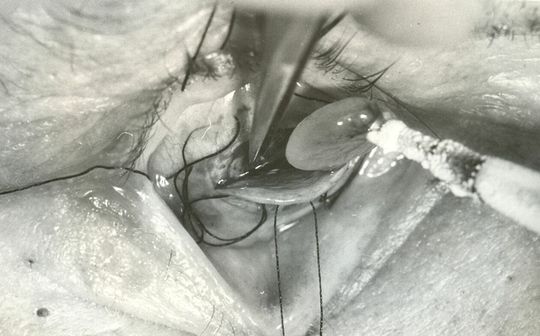

Zdjęcie: Operacja chirurgiczna oka dawnymi narzędziami

Operacja chirurgiczna oka dawnymi narzędziami

Autor: Archiwum UML